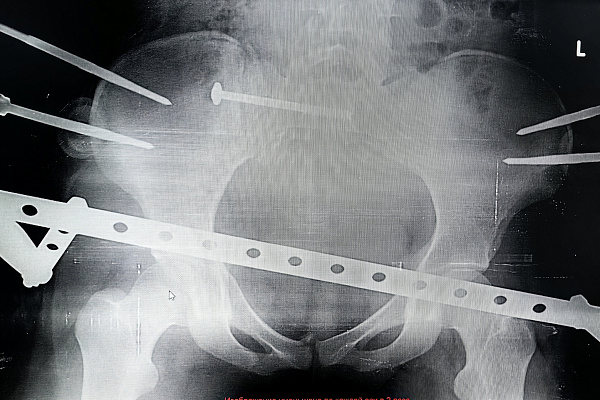

-Хотя по возрастной классификации 17-летние ещё считаются подростками, многие подходы детской травматологии и ортопедии в таком пограничном возрасте уже не эффективны. Поэтому решение приходится искать среди вариантов, применимых ко взрослому населению. В данном случае мы остановились на сложной и довольно редкой операции - малоинвазивном комбинированном остеосинтезе таза. Нам удалось с помощью внешней конструкции и имплантируемых элементов зафиксировать повреждённые крестцовую, лонную и седалищную кости. И при этом обойтись без травматичного доступа. То есть вся операция была выполнена без разрезов, - объясняет заведующий отделением травматологии и ортопедии №1 Сергей Глиняный.

Основные риски были связаны с установкой илеосакрального блокирующего винта в области крестца, где проходят нервы, спинной мозг и множество сосудов. Критически важно не задеть эти структуры, поэтому операция требует от врача соответствующего опыта и высокого уровня мастерства.